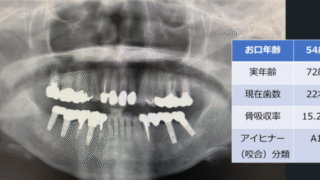

人工知能と歯科⑥【お口年齢AIの開発】

本記事では、この度歯科エックス線画像を用いた「お口年齢AI」の開発と特許出願を行いましたので、その内容について解説させて頂きます。プレスリリース(PRTIMES 2025年10月28日)はこちらお口年齢AIとは「お口年齢AI」は、歯科パノラ...